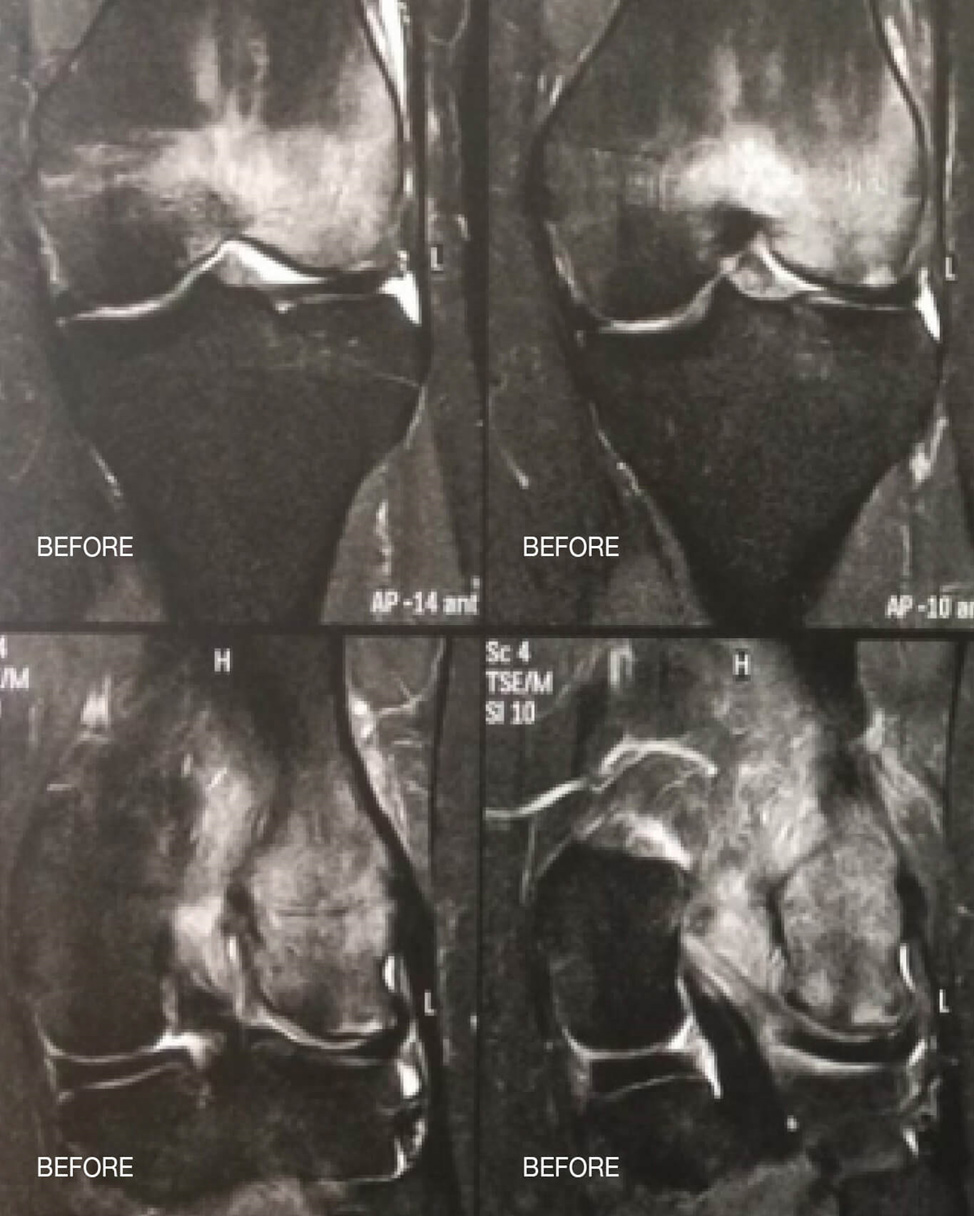

Las siguientes imágenes muestran un edema medular en la articulación de la rodilla antes y después de la terapia papimi. El tratamiento tuvo éxito tras sólo 10 sesiones.